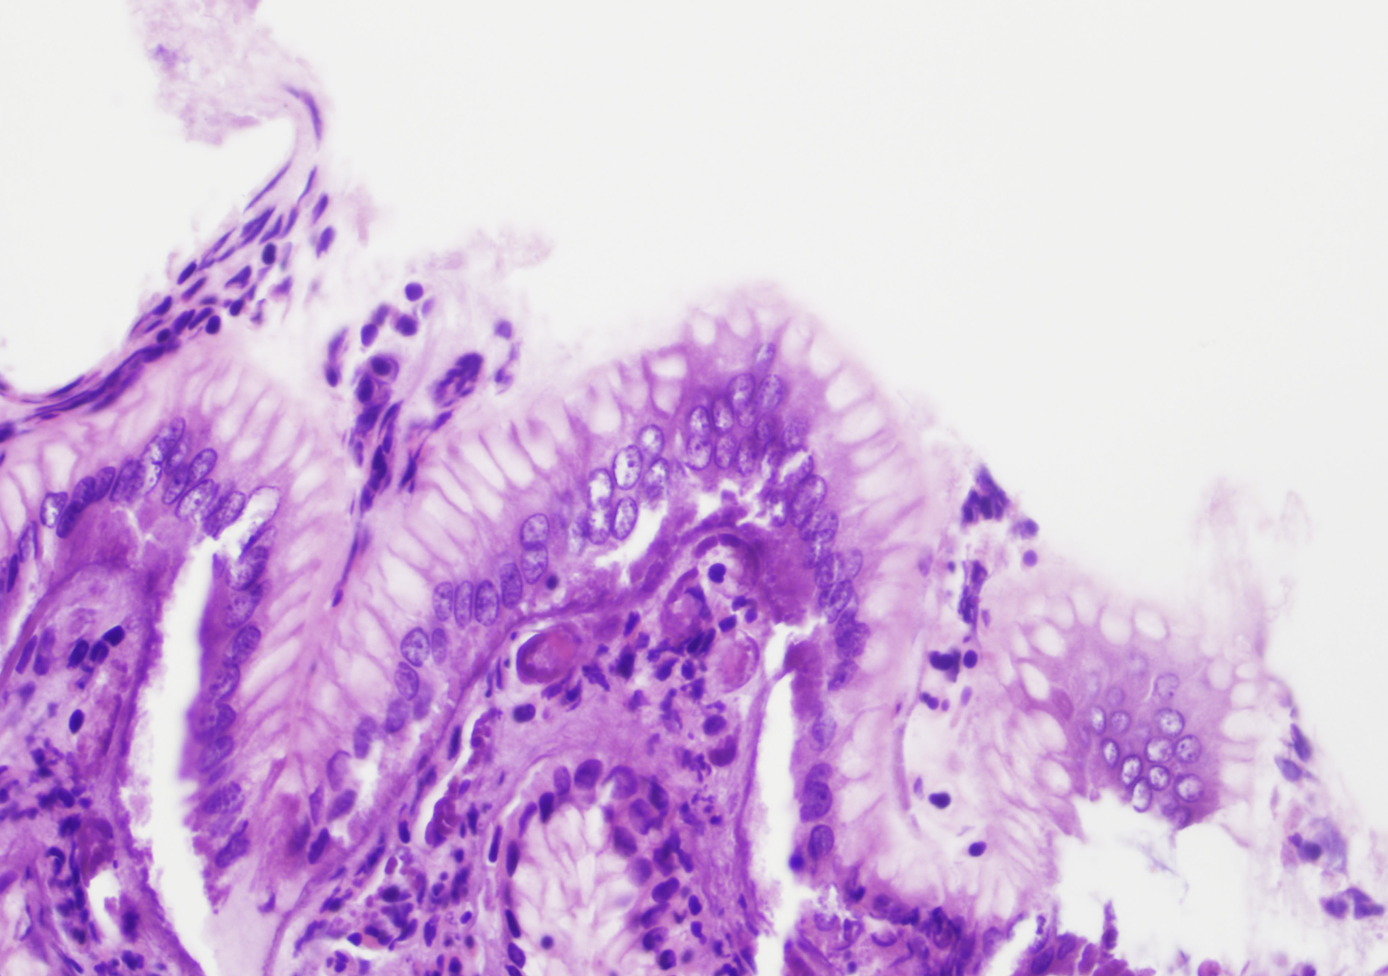

dysplasie des cryptes (dysplasie dans les cryptes et maturations en surface, photo)